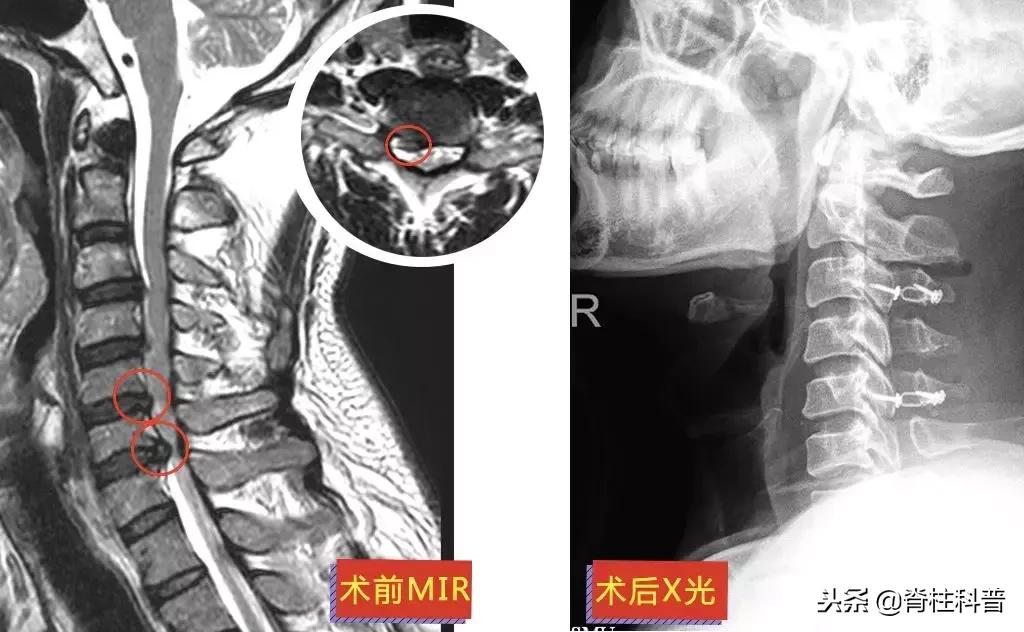

▲ 黄三叔:术前MRI与术后X光